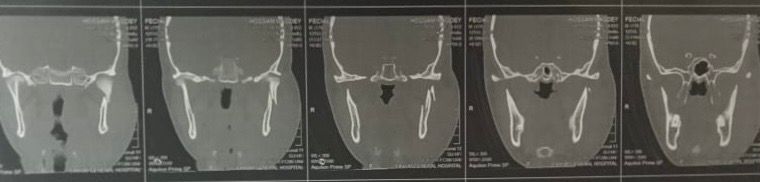

نجح فريق جراحة الوجه والفكين بمستشفى الفيوم العام في إجراء تدخل جراحي دقيق لشاب يبلغ من العمر 25 عامًا، أُصيب بكسر في لقمة مفصل الفك بالجهة اليسرى، إثر تعرضه لحادث سير.

واستقبل المستشفى المصاب بقسم الطوارئ، حيث جرى تقييم حالته الصحية وتجهيزه للتدخل الجراحي العاجل وتم إجراء العملية بنجاح، وشملت رد وتثبيت الكسر باستخدام شرائح ومسامير معدنية، إلى جانب عمل غرز تجميلية للجرح تحت تأثير التخدير الكلي.

وأسفرت الجراحة عن استعادة الوظيفة الحركية لمفصل الفك بشكل كامل، دون حدوث أي تأثير على العصب السابع، كما تحسنت حالة المريض وغادر المستشفى بعد الاطمئنان على استقرار وضعه الصحي.